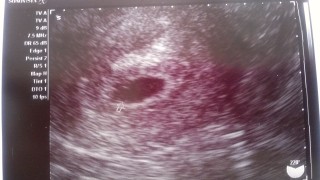

3月2日に初診。

その際は陽性反応はあるものの

胎嚢は見えませんでした。

不安のまま今日3月14日再受診すると

無事胎嚢見えました(*^^*)

来週また来てねと言われたので

その時は胎芽とか確認出来るといいな♪